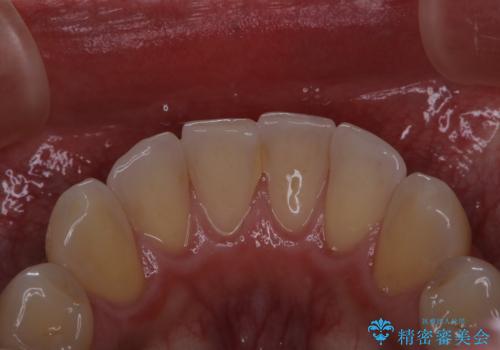

電子タバコによる着色をPMTCできれいに落とす

- 1日に10本くらい電子タバコを吸うため、歯の黄ばみ・着色が気になるとのことでした。PMTC30分コースを行いました。

タバコに含まれているものの中で、タールというものが歯の黄ばみの原因です。その黄ばみなどを、無理に落とそうとしたりすると歯の表面に傷がついてしまったり余計に汚れがつきやすい状態になることがあります。

PMTCでは、歯の表面の凸凹にミネラルを補給して、ツルツルの表面に仕上げます。定期的にPMTCを行うことにより、歯質の強化になり着色がつきにくい状態になります。